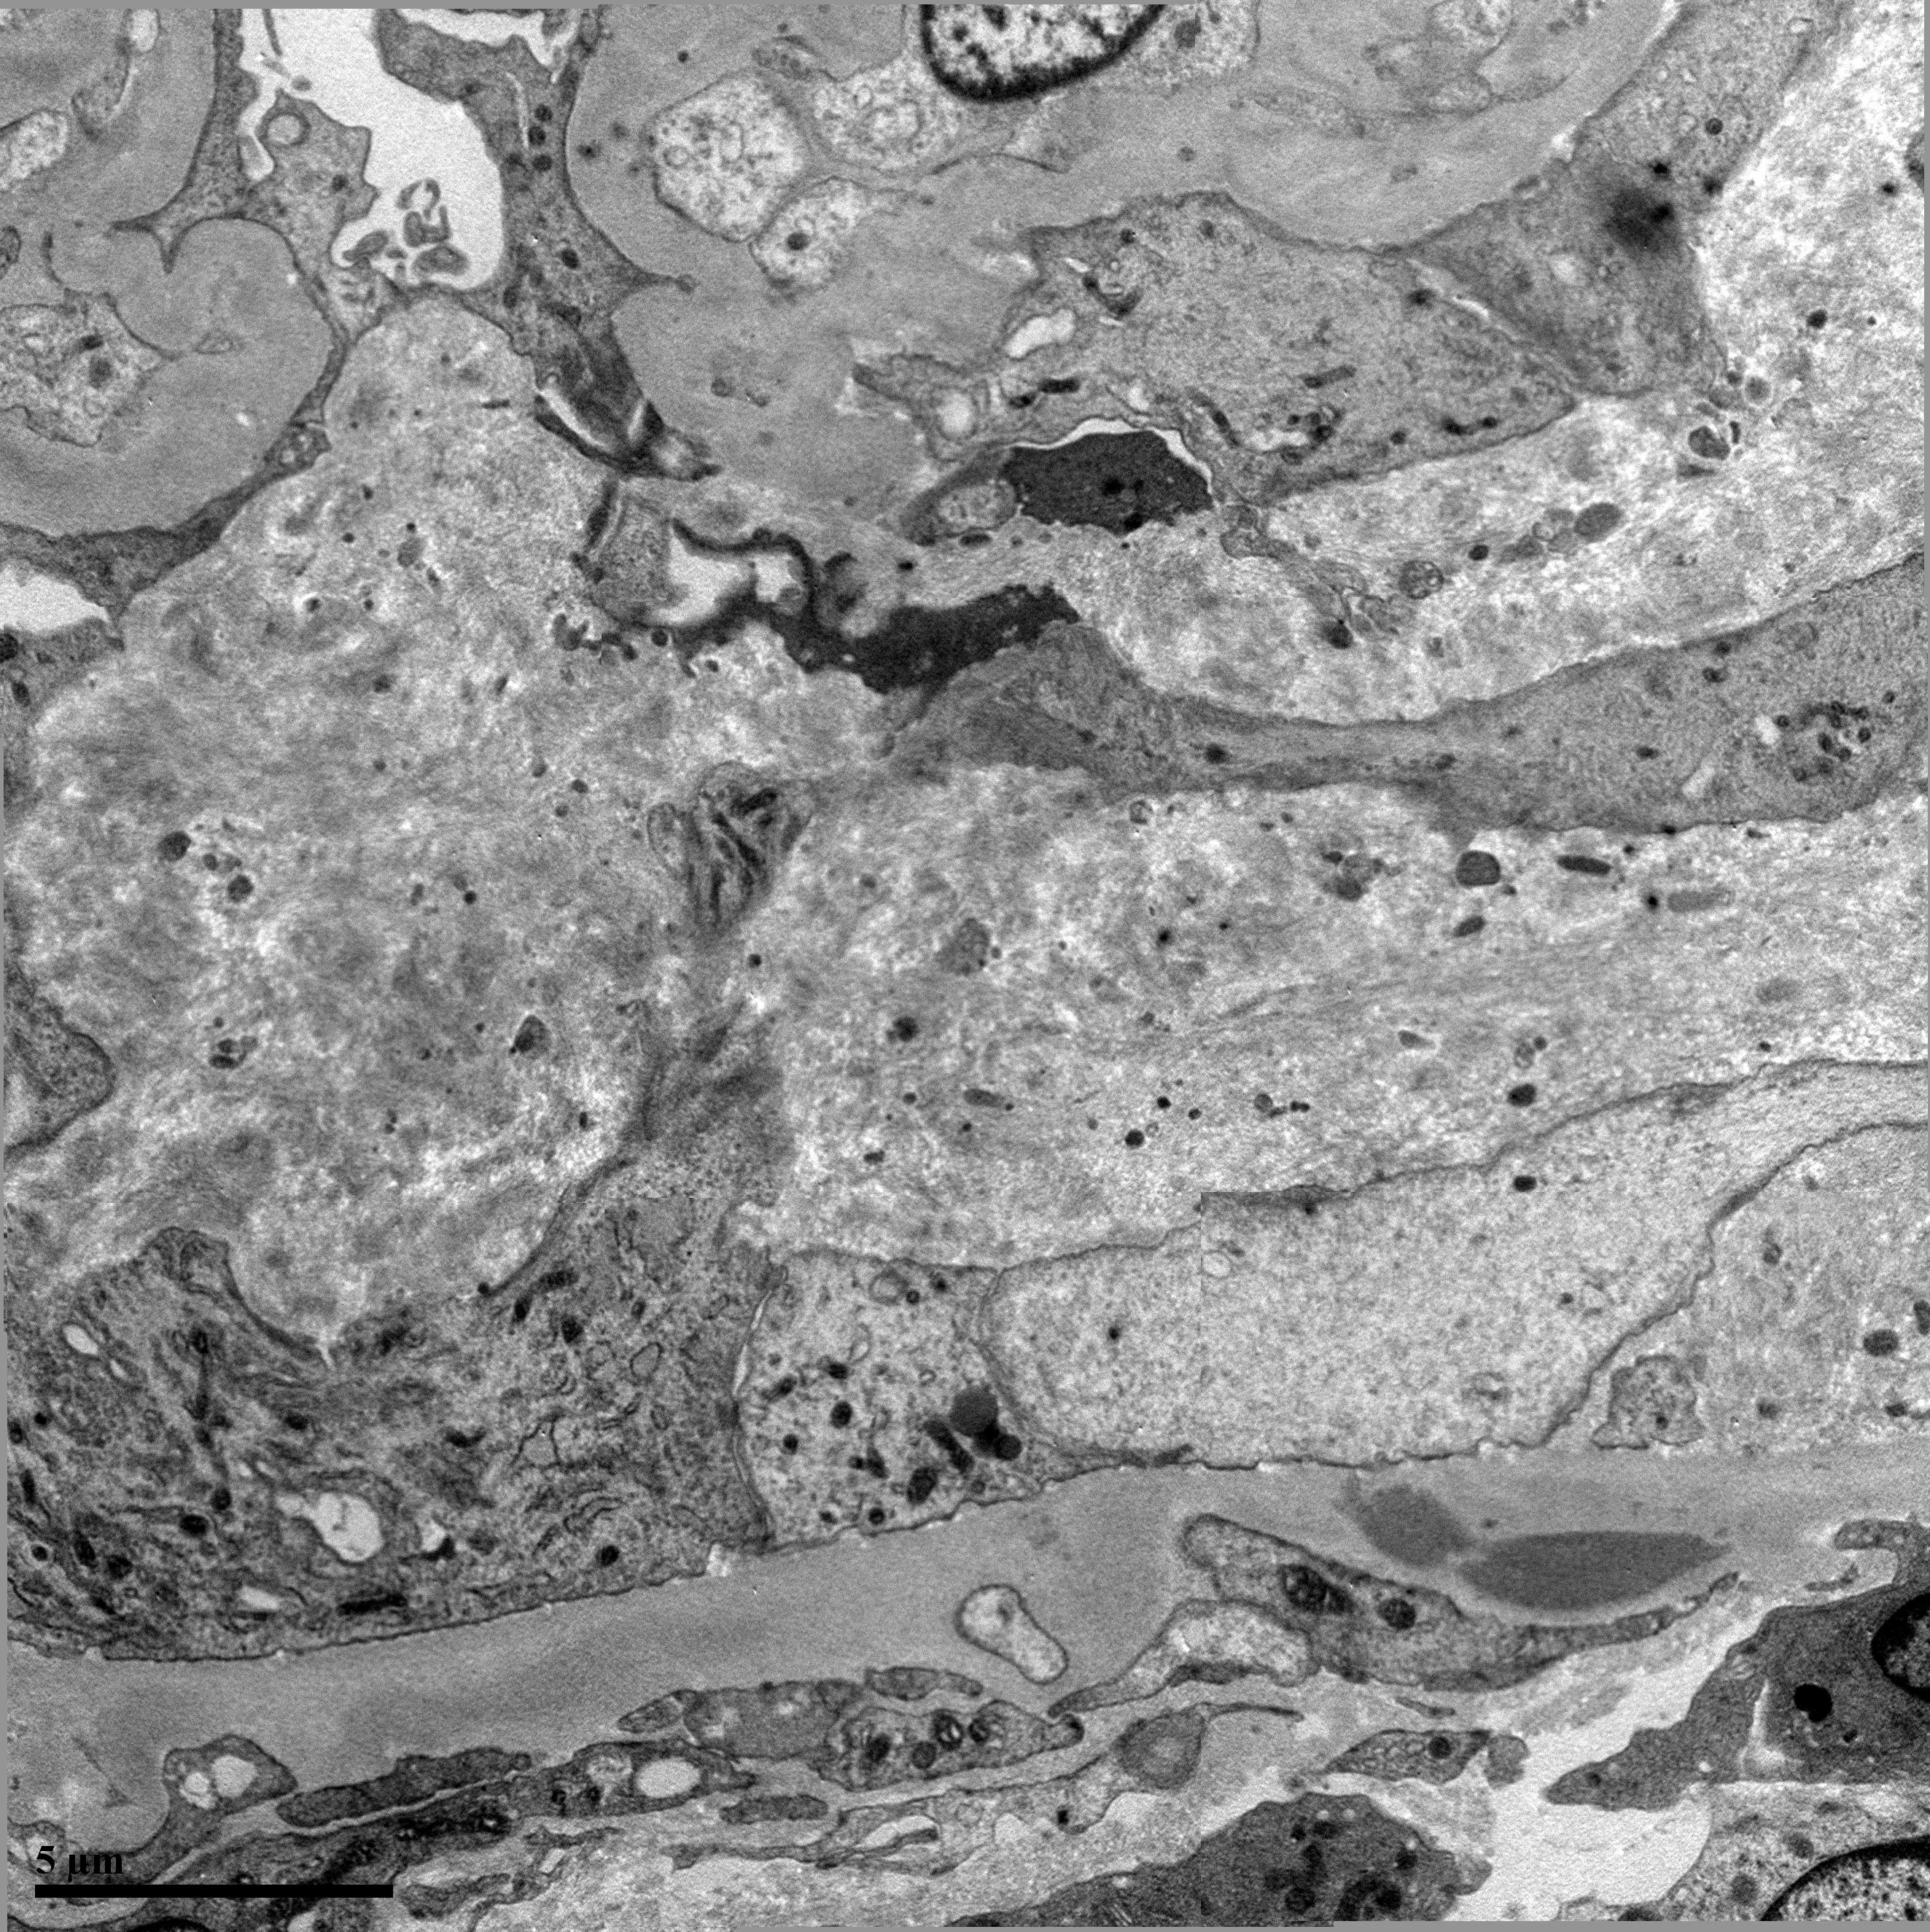

На наш взгляд, данный клинический случай представляет интерес по нескольким причинам. В первую очередь вызывало сомнение наличие у пациента гломерулонефрита, поскольку, несмотря на иммуногистохимическое описание нефробиоптата, имеется несколько противоречивых моментов: во-первых, первоначально диагноз гломерулонефрита был заподозрен на основании лишь однократного изменения в ОАМ, во-вторых, у пациента произошла спонтанная нормализация функции почек при отсутствии какого-либо специфического лечения гломерулонефрита. В связи с наличием вышеописанных противоречий нефробиоптат был пересмотрен морфологом ФГБУ РостГМУ: заключительная гистологическая картина более соответствует фокальному гломерулосклерозу с компенсаторным мембранопролиферативным процессом в клубочках. Признаки умеренно выраженной гипертензивной ангиопатии (рис. 4 а–в). Присутствует один среднего размера лимфогистиоцитарный инфильтрат (признаков системного воспалительного ответа в представленных препаратах нет). По данным электронной микроскопии нефробиоптата – утолщение базальной мембраны клубочков, местами значительное. Обширные поля сглаживания малых отростков подоцитов (рис. 5).

Рис. 5. Электронная микроскопия нефробиоптата (окраска – импрегнация серебром, Ч10 000). Утолщение базальной мембраны клубочков, местами значительное. Обширные поля сглаживания малых отростков подоцитов.